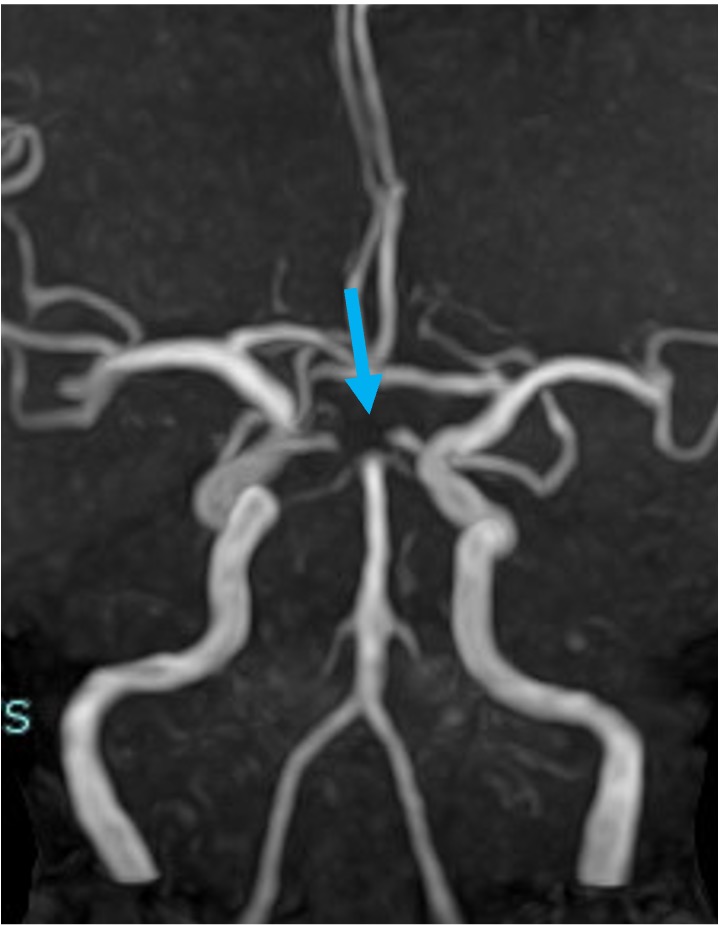

当院で行われた症例を提示いたします。80歳、女性、くも膜下出血の患者様。血管撮影にて図1〜4赤矢印の様に脳底動脈に広頸のネックを伴う不整形の瘤を認めました。母血管の蛇行狭窄が強く、マイクロカテーテルが複数入りにくい状態だったのでWEB(図5〜8黄色矢印)を用いて治療を行いました。術後MRAでも図10青矢印の様に動脈瘤は描出されません(図9は術前MRA)。現在も出血なく経過しております。

図9 |